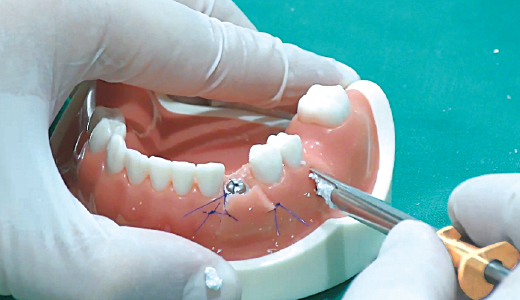

3. Bone Carrier로 골이식재 수집

-